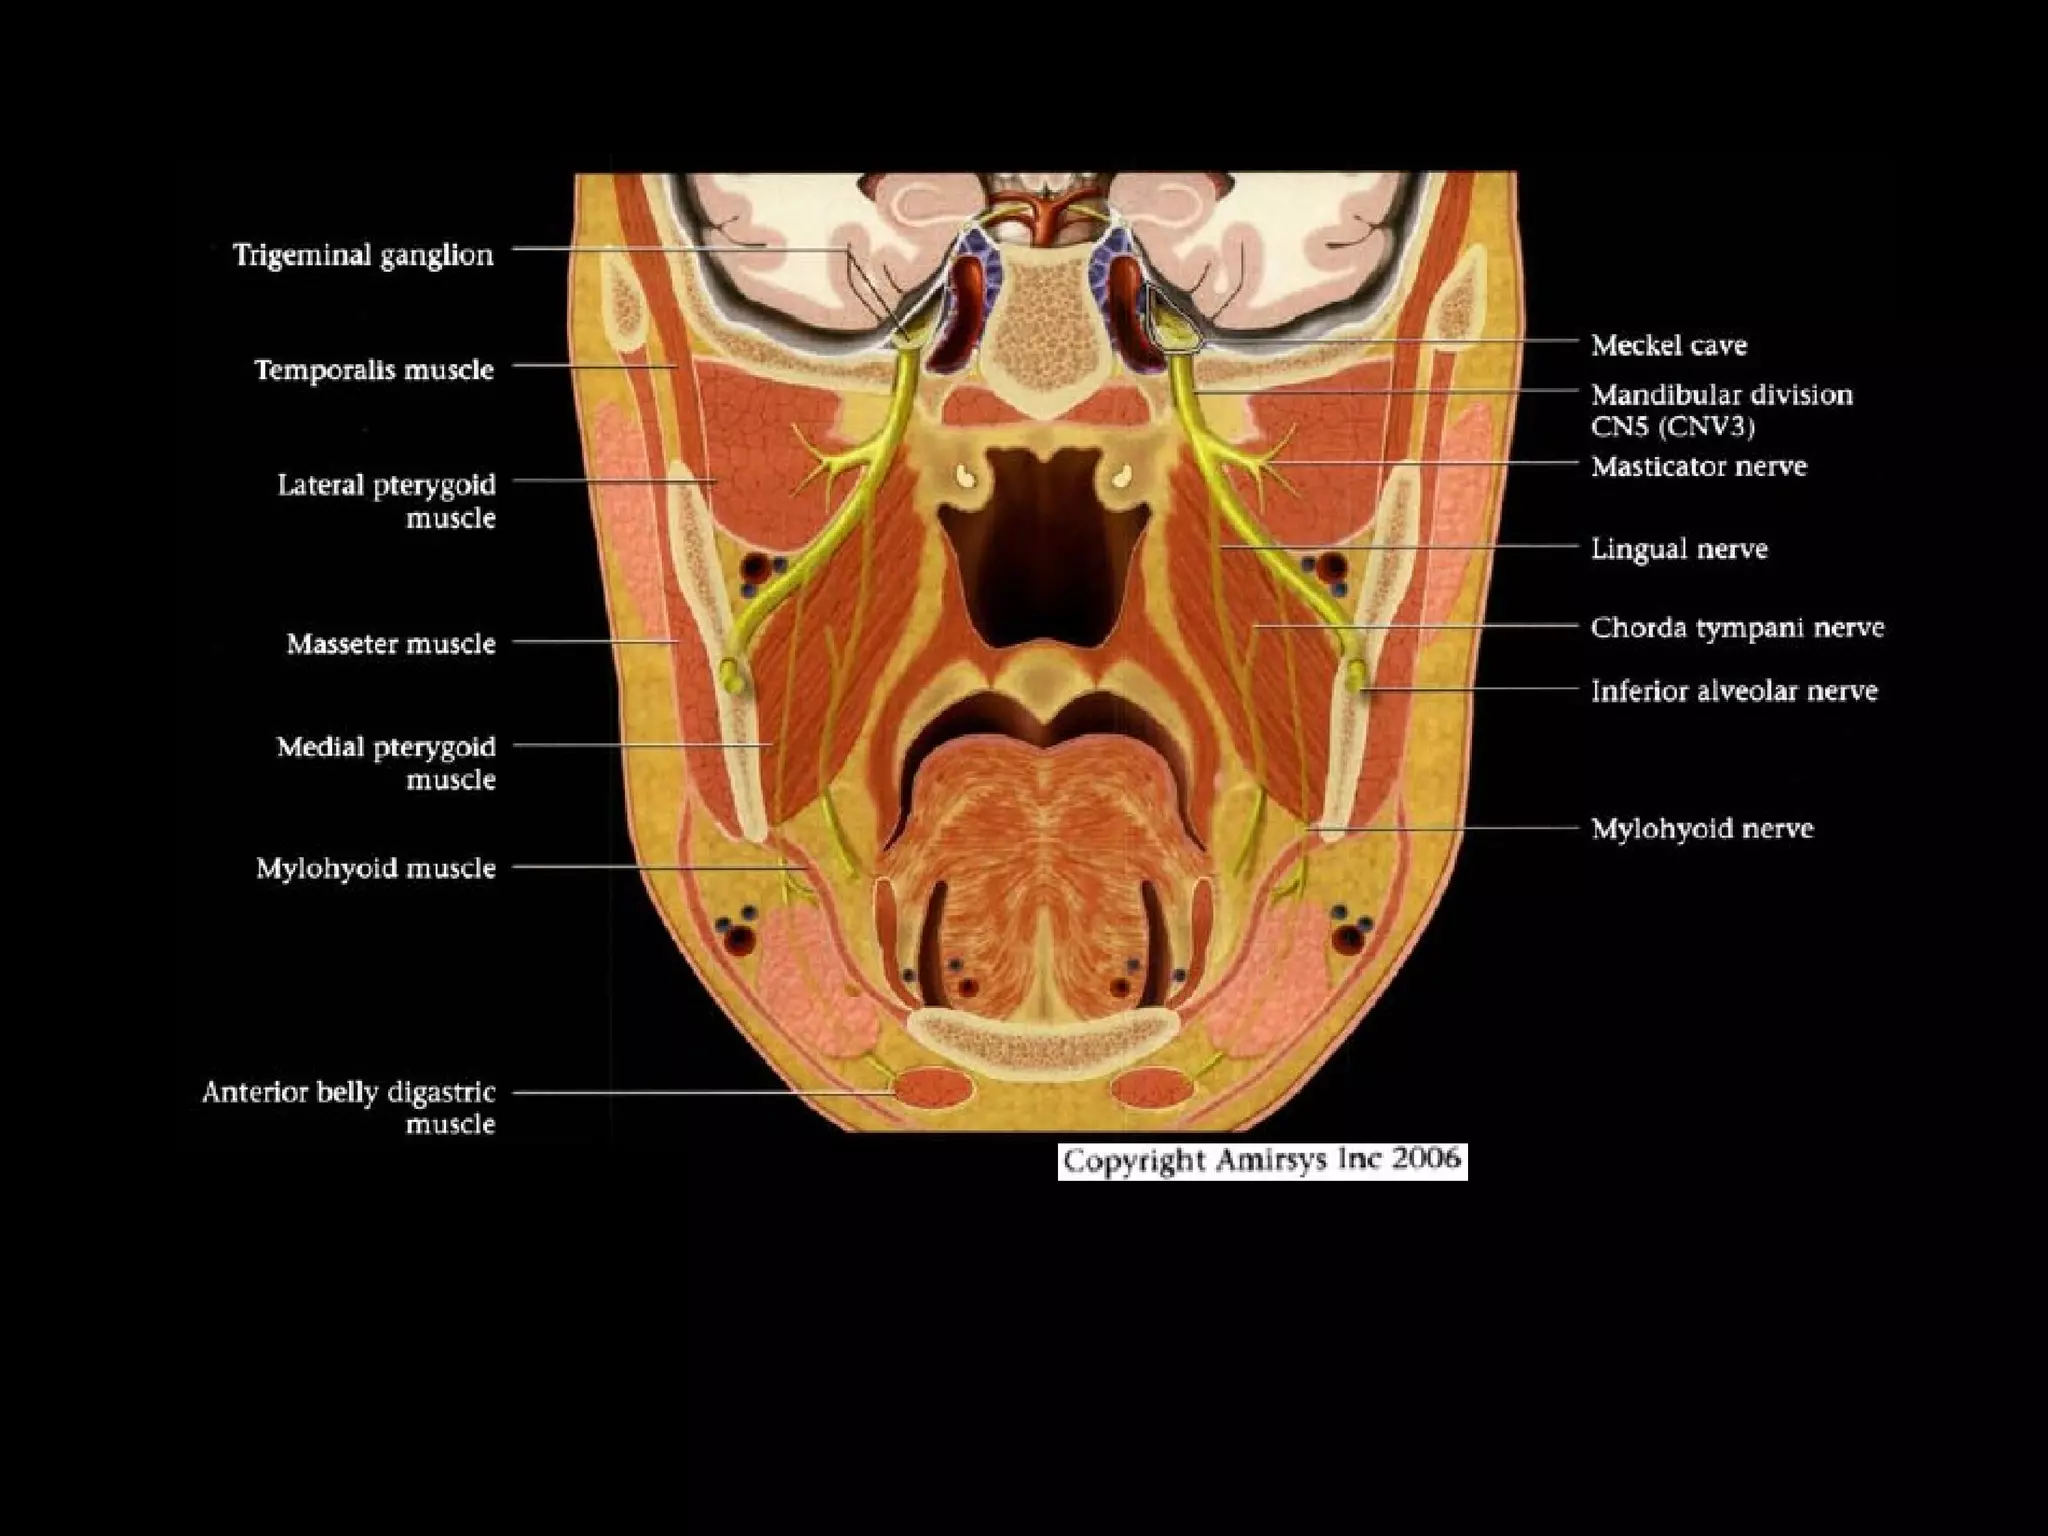

Divisions (Post-Ganglionic) of CNS

Mandibular nerve (CNV3)

• Does not pass through cavernous sinus

• Exits directly from Meckel cave, passing inferiorly

through foramen ovaIe into masticator space

• Carries both motor and sensory fibers

- Motor root bypasses TG, joins V3 as it exits through

foramen ovale

- Divides into masticator (muscles of mastication) and

mylohyoid nerves (mylohyoid and anterior belly of

digastric muscles)

- Masticator nerve take off just below skull base

- Mylohyoid nerve take off at mandibular foramen

• Main sensory branches include inferior alveolar, lingual

and auriculotemporal nerves